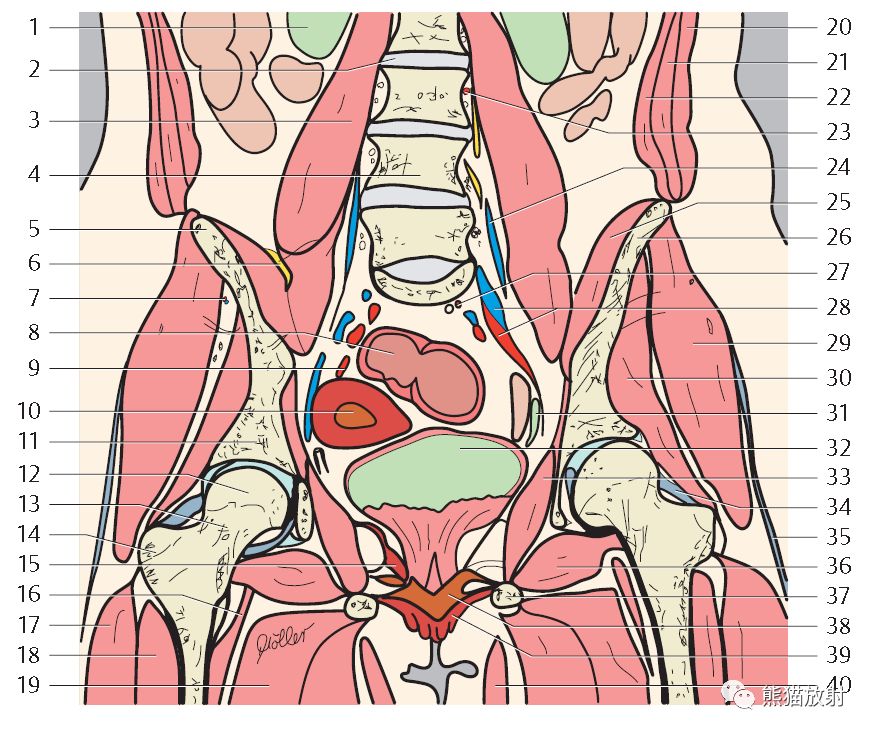

系统解剖图

↑ 女性盆腔器官(前上面观)

冠状T2WI

1、右肾,2、L2/3椎间盘,3、腰大肌,4、第4腰椎(L4),5、髂嵴,6、股神经,7、臀上动/静脉,8、乙状结肠,9、子宫动脉,10、子宫(腔),11、髋臼顶(髂骨体),12、股骨头,13、股骨颈,14、大转子,15、肛提肌,16、髂腰肌,17、股外侧肌,18、股中间肌,19、大收肌,20、腹外斜肌,21、腹内斜肌,22、腹横肌,23、腰动/静脉,24、髂腰动/静脉,25、髂肌,26、髂骨(翼),27、直肠上动脉,28、髂内动/静脉,29、臀中肌,30、臀小肌,31、输尿管,32、膀胱,33、闭孔内肌,34、髂股韧带,35、髂胫束,36、闭孔外肌,37、坐骨(支),38、会阴深横肌,39、小阴唇,40、股薄肌;

41、椎前淋巴结,42、岬角淋巴结;43、髂内淋巴结,44、阴道旁淋巴结,45、膀胱后淋巴结。